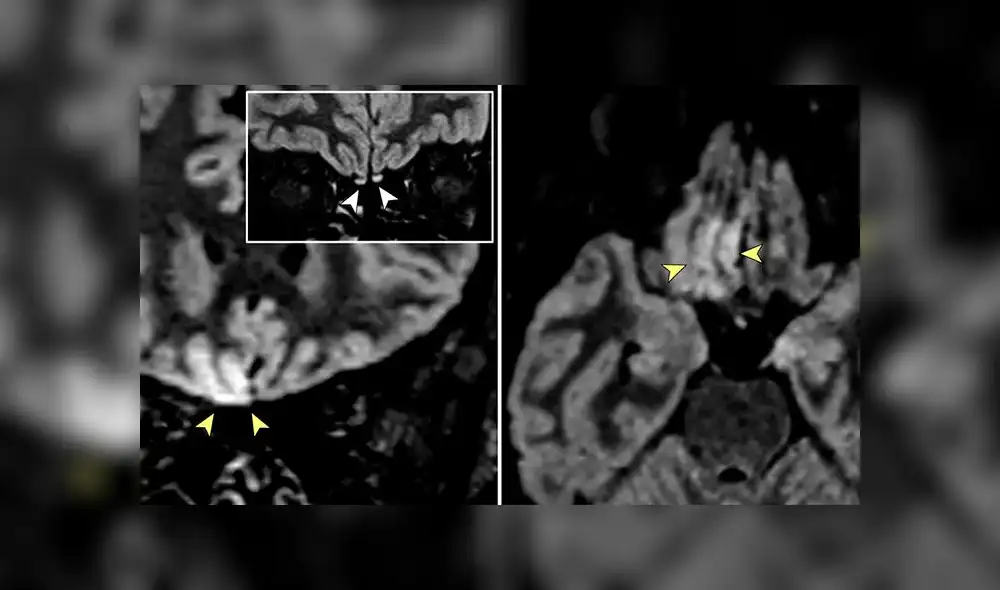

Imágenes que muestran la resolución completa de la alteración de la señal vista anteriormente dentro de la corteza del giro recto derecho. Foto: JAMA Neurology

El estudio, publicado el 29 de mayo pasado, mostró que la italiana —radióloga que estuvo trabajando en una sala de COVID-19— tenía una inflamación en el bulto olfatorio, la estructura neutral del cerebro involucrada en el sentido del olfato.

“Según los hallazgos de la resonancia magnética, incluidos los ligeros cambios en el bulbo olfativo, podemos especular que el SARS-CoV-2 podría invadir el cerebro a través de la vía olfatoria y causar una disfunción olfatoria de origen neurosensorial”, concluyeron los expertos.